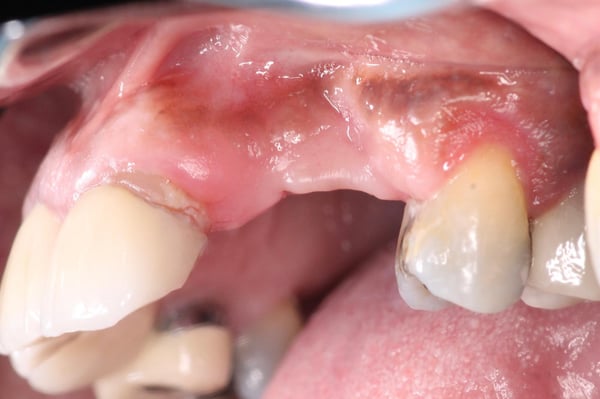

A palatal full thickness flap confirmed our suspicion. The root fragment was removed, the defect was degranulated, and the implant surface was decontaminated with a Nd:Yag laser.